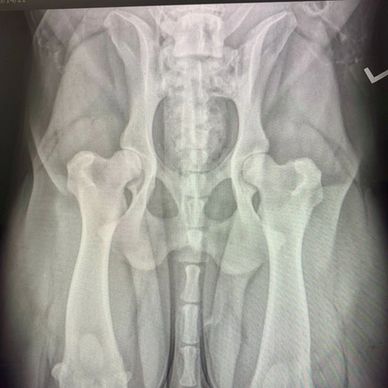

Parent testing

When our dogs reach maturity we get their hips and elbows screened from the Orthopedic Foundation of Animals(OFA). They are screened for hip dysplasia with hip joint irregularities and early arthritis detections.